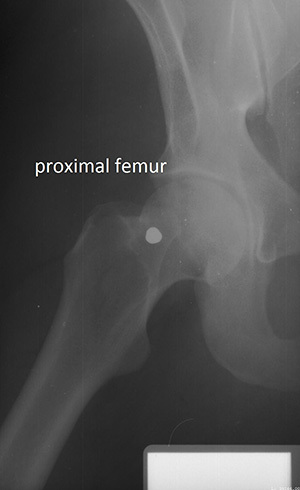

The researchers compared ante-mortem and post-mortem lateral craniofacial (side of the skull) X-rays for 20 individuals; X-rays of the vertebral column (spine) for 50 individuals; and X-rays of the proximal femur (upper leg) for 23 individuals. They used these evaluations to develop location-specific standards for each skeletal region.

A side X-ray of the skull could be used to identify a body with 97% certainty and a 10% misclassification rate based on as few as two specific traits — as long as there were no inconsistencies in the shapes of the skull X-rays. Cervical (neck) vertebrae provided greater than 98% certainty and a 7% misclassification rate based on a single trait.